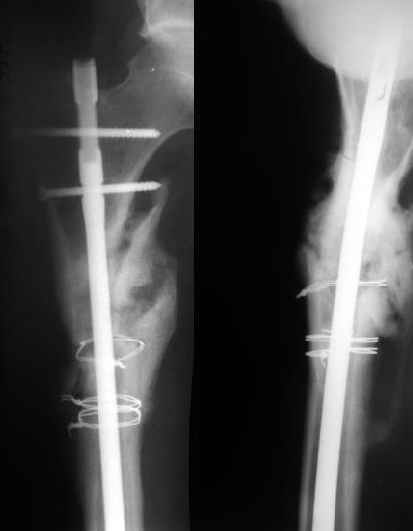

В районной больнице больному выполнен остеосинтез обоих бедер штифтом Кюнчера и накостный остеосинтез правой плечевой кости. Через год больной поступил к нам с ложным суставом шейки левого бедра, обеих бедер и правой б/б кости. Нами выполнено остеосинтез правой голени и левого бедра пластиной Абдуразакова (угольникообразная пластина) с аутокостной пластикой (трансплантат 1/3 ширины малоберцовой кости, длиной 12-14 см.). Через 6 месяцев в связи жалоб больного на хруст, боль и не возможность сидеть, больному произведено цервикокапитальное эндопротезирование головки левого бедра. Больной не посоветовавшись с нами, активно стал разрабатывать левый коленный сустав, в результате через 3 месяца после последней операции поступил с изломом пластины (рис.1). На наш взгляд, оптимальным решением было выполнение остеосинтеза блокирующими гвоздями обеих бедер (рис2). Это первые операции с использованием подобных гвоздей (получили по гум.помощи), поэтому практики по использованию их у нас нет.1. используются ли эти гвозди при ложных суставах?2. Больной в течение этих лет не ходит, можно ли его ставить на ноги?3. Как вести дальше этого больного?4. Какие возможно были варианты остеосинтеза, кроме реэндопротезирования ревизионной ножкой?Заранее благодарю, Алишер.

На данный момент правая голень срослась, больной активен в пределах постели. Второе(правое) бедро стабилизированное (рис. до и после). движения в коленном суставе: сгибательная контрактура правого коленного сустава 90, левого 145.

1) Мы бы не убирали проволоку, и вообще не вмешивались открыто на очаге - это ничего не даст, кроме ухудшения кровоснабжения концов отломков. Если просто закрыто перештифтовать при подобной картине, лучше с рассврливанием - это по нашему опыту дает сращение в 100%. В приложении пример - болезненное несращение более года, результат через полгода.

1

2

2)запирающие винты выглядят чрезмерно короткими. А им бы тут надо хорошо держаться за оба кортекса. Это в проксимальном отломке можно ввести было только динамический винт, или вообще винты не вводить.